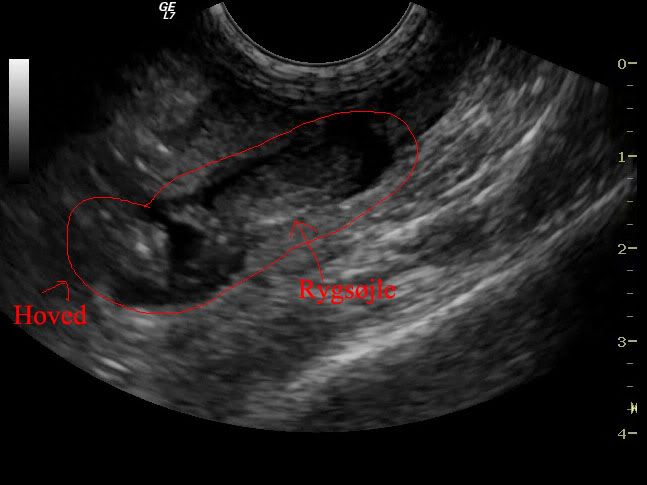

Og her har jeg tegnet rundt om den så folk kan navigere

Og så nok det bedste screenshot jeg kunen tage, jeg synes den er ret tydelig :D Den ligger med ryggen til

med streger